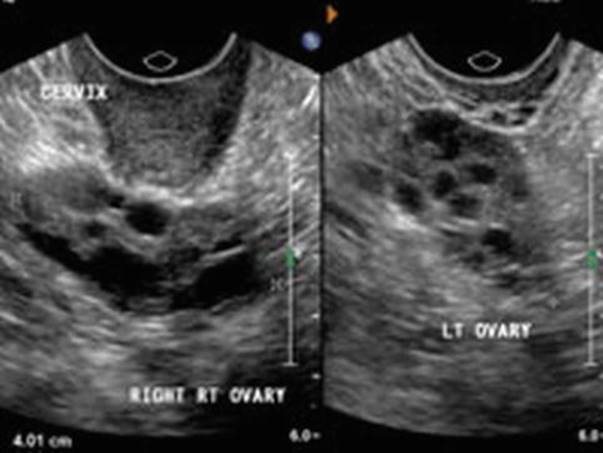

Assessment of ovarian reserve by ultrasound is done by measuring the AFC (Fig. 2.1), ovarian volume (Fig. 2.2), and stromal blood flow (Fig. 2.3), which will help us in predicting the ovarian response to controlled ovarian stimulation (COS). The number of antral follicles correlates well with the woman’s age, ovarian reserve, and ovarian response to gonadotropin stimulation. As the ovary ages and the ovarian reserve decreases, there is a noticeable reduction in the ovarian volume and the number of antral follicles. An AFC of less than 5 and/or ovarian volume of less than 3 cm3 is a good marker to predict poor ovarian response to COS in assisted reproduction programs (ART). There could be some intercycle variability in the AFC. Seventy-one percent of variation is due to intra subject examination and only 29 % is due to individual cycle variation.

Fig. 2.1

Antral follicle count

Fig. 2.2

Ovarian volume

Fig. 2.3

(a, b) Stromal blood flow

The AFC can be evaluated either using the 2-dimensional (2D), 3-dimensional (3D), or 4-dimensional (4D) ultrasonography (USG) (Sono AVC – hypoechoic aspect of the ultrasound display is inverted to demonstrate fluid-filled areas within the 3D dataset). Sono AVC (Fig. 2.4) is the best model for predicting the number of oocytes retrieved with a retrieval rate of 60 %. AFC is a good predictor of response but not of pregnancy. The optimum cut-off value of AFC for poor response is ≤10 but the post-test probability was reported to be the highest at cut-off levels of <8 [1].

Fig. 2.4

Sono AVC

The optimum cut-off value for hyper-response of AFC is ≥14 with a sensitivity of 82 % and specificity 89 % to predict ovarian hyperstimulation syndrome (OHSS). The ovarian volume also correlates with the number of growing follicles, but not with the number of oocytes retrieved [2]. It was also observed that women with small ovaries with a volume of less than 3 cm3 have a very high cancellation rate of in vitro fertilization (IVF) [3]. 3-dimensional ultrasound allows more precise calculation of ovarian and stromal volumes (Fig. 2.2). However, yet again, the predictive value for pregnancy by measuring the ovarian and stromal volume is limited (1.0–1.4) [4, 5].

Stromal Blood Flow (Fig. 2.3a, b)